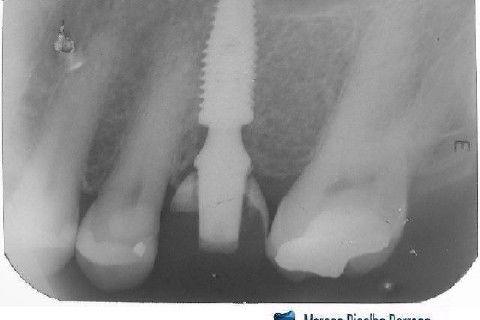

Instalação de um implante em região do 26. Utilizamos um implante cone morse Alvim Neodent 4.3 X 11,5. Foi uma cirurgia muito rápída e minimamente traumática, sem retalho e sutura.